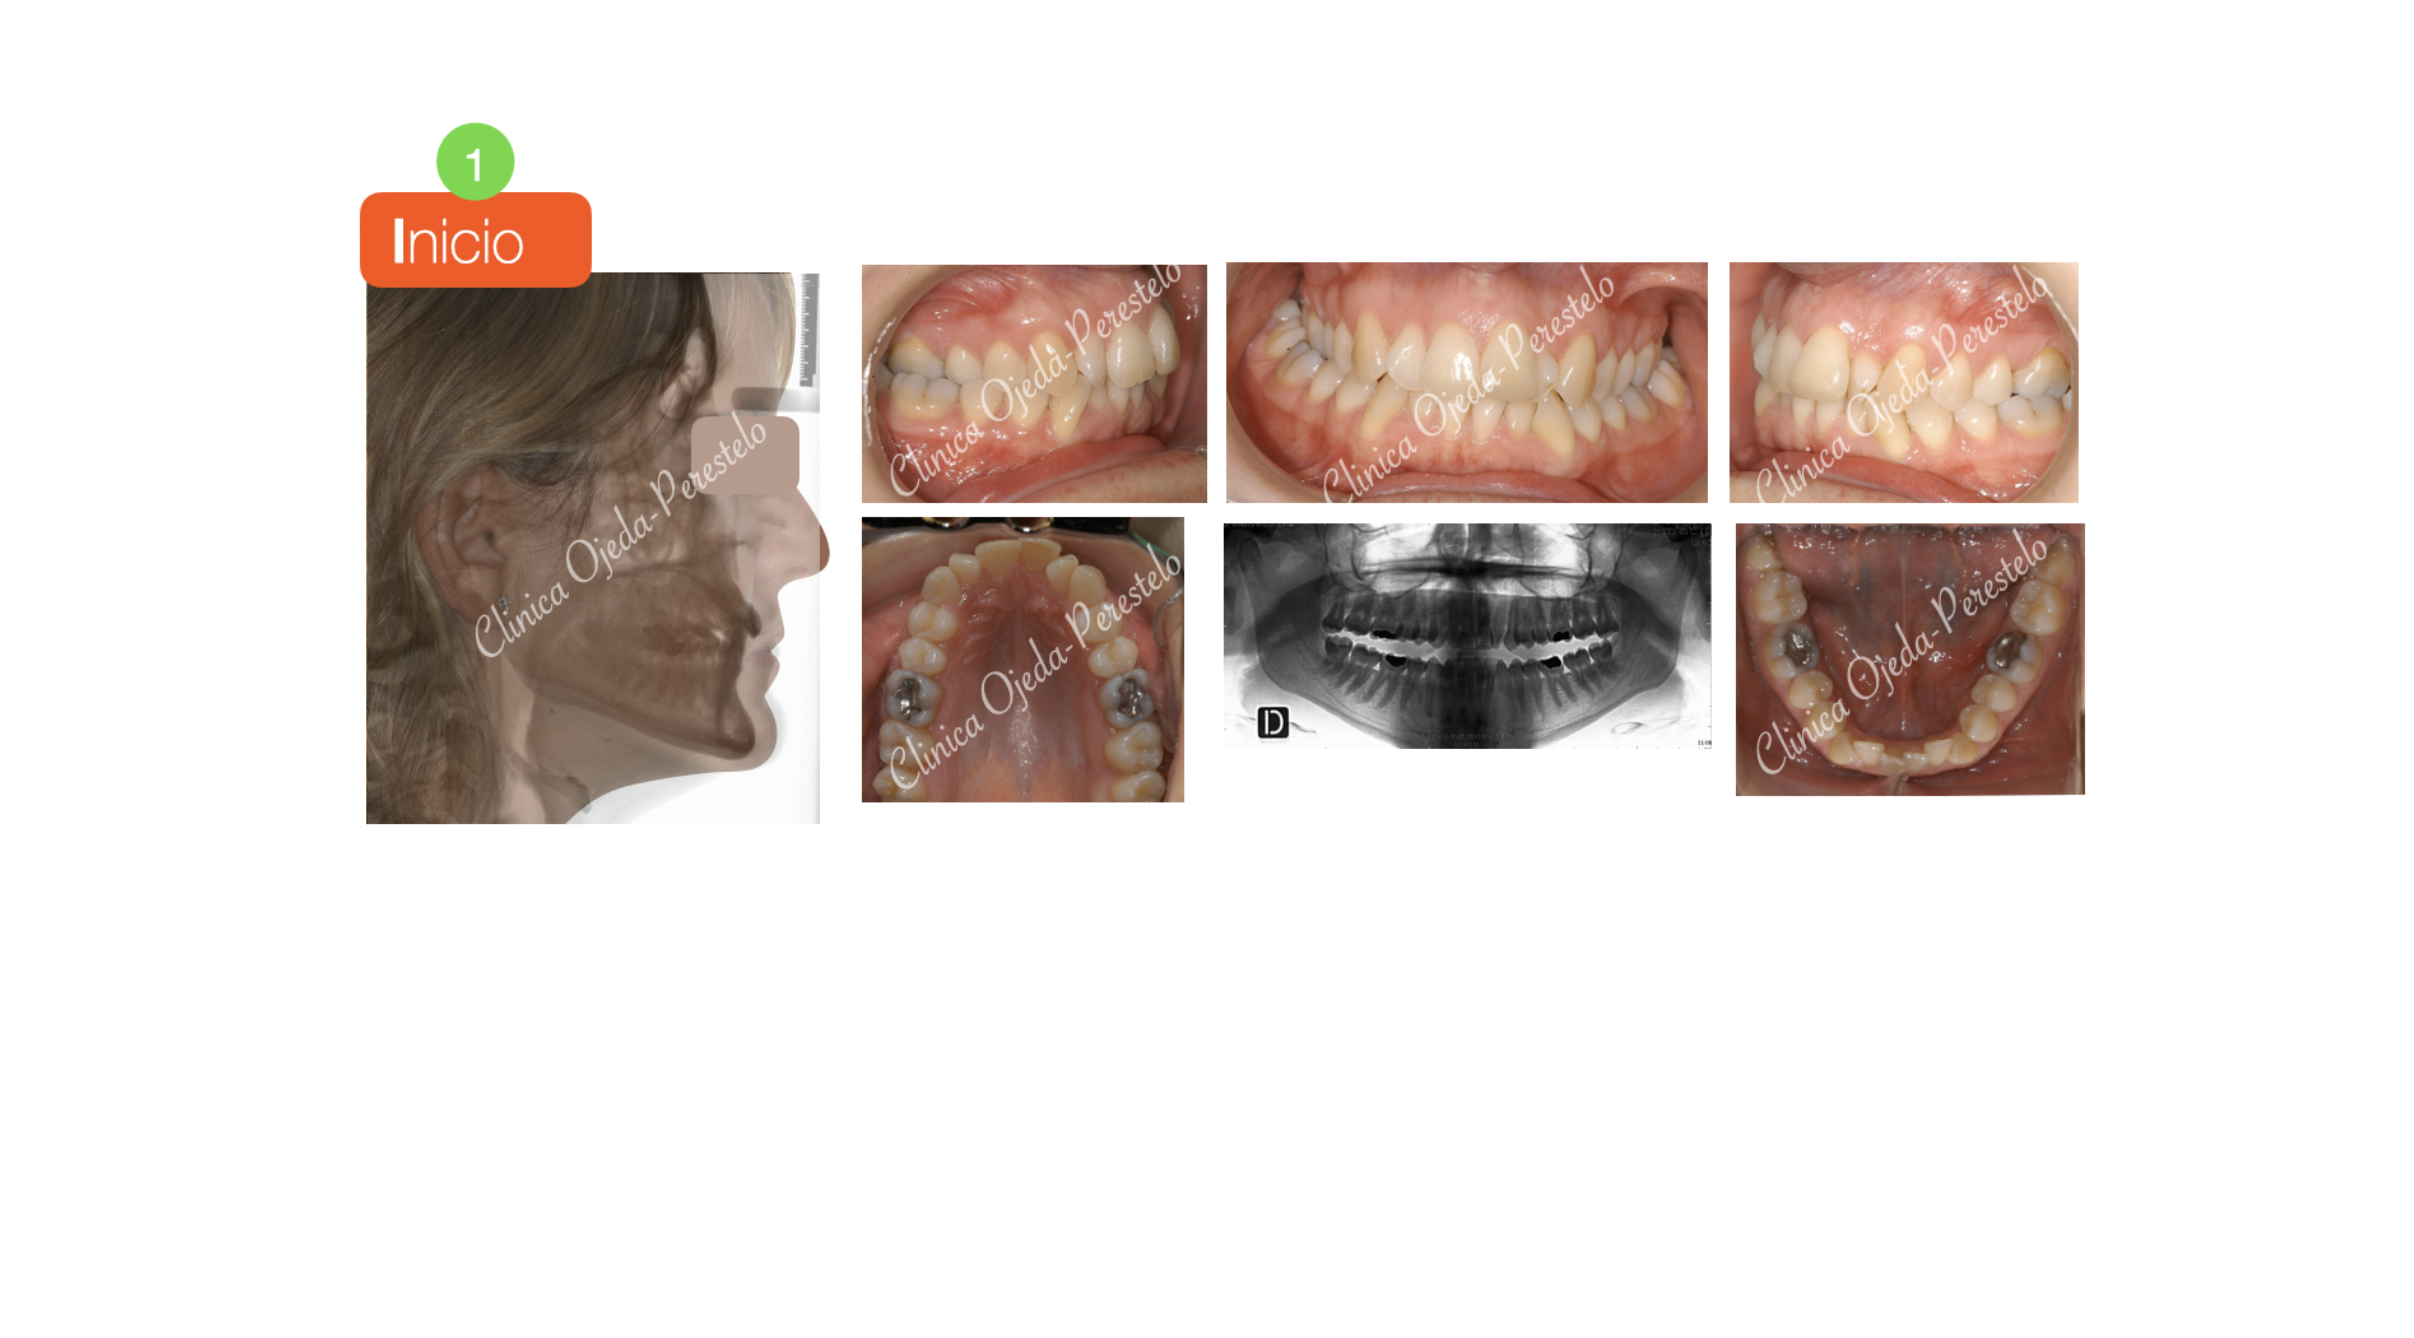

Paciente que consulta por mordida cruzada bilateral y apiñamiento severo.